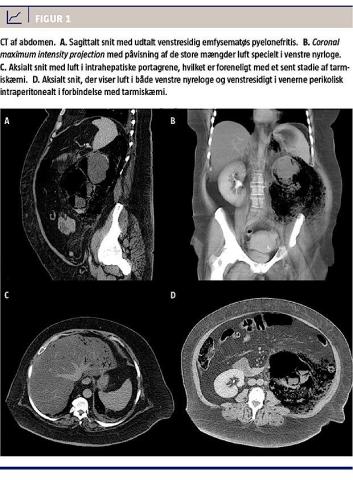

En CT med intravenøs kontrast i kombineret venøs fase og udskillelsesfase på indlæggelsesdagen afslørede en cystisk struktur (ca. 16,8 cm i største længde) i venstre nyreloge, den havde lidt randopladning og blev tolket som værende nyren med massivt væskeindhold og luftvæskespejl, hvilket tydede på diagnosen EPN (Figur 1). Derudover viste CT’en en mistænkelig tæt relation mellem colon descendens og den cystiske struktur samt luft i de portomesenteriske vener. Der blev ikke fundet tegn på stenose eller obstruktion af de mesenteriske arterier eller vener.